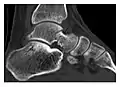

Figure 7: Fatigue fracture of the talus in a 25-year-old male basketball player with right hind foot and ankle pain, without history of trauma, and a normal initial radiograph (not shown). (a) One-month followup lateral radiograph shows normal appearance. (b) Sagittal T1-weighted MRI shows an irregular fracture line (arrow) within an ill-defined area of hypointensity corresponding to bone marrow edema.[1]